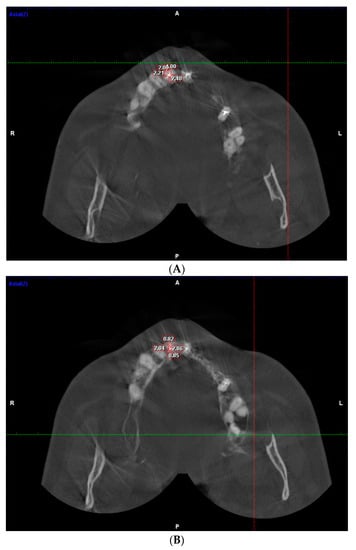

2. Materials and Methods

3.3. Dentinal Thickness in Apical Part